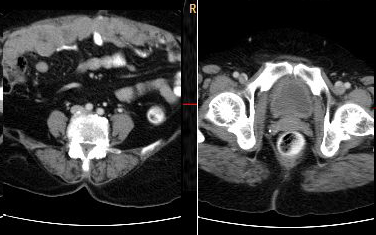

Stage 3: peritoneal implants outside pelvis or inguinal or retroperitoneal lymphadenopathy. Implants can be omentum, liver, parietal peritoneum. Peritoneal dissemination is characterised by peritoneal thickening, nodular lesion, stellate nodules located within mesentery or omentum. Stage 3a, b, c differ in size of lesion- 3a-tumour grossly limited to pelvis and gross ascites; 3b-peritoneal implant 2cms or less; 3c-implant size is more than 2cms . Retroperitoneal and inguinal adenopathy qualifies as stage 3c (Figures 6, 7 & 8).

Figure 8: Two different cases of carcinoma of ovary with omental and peritoneal thickening stage 3.